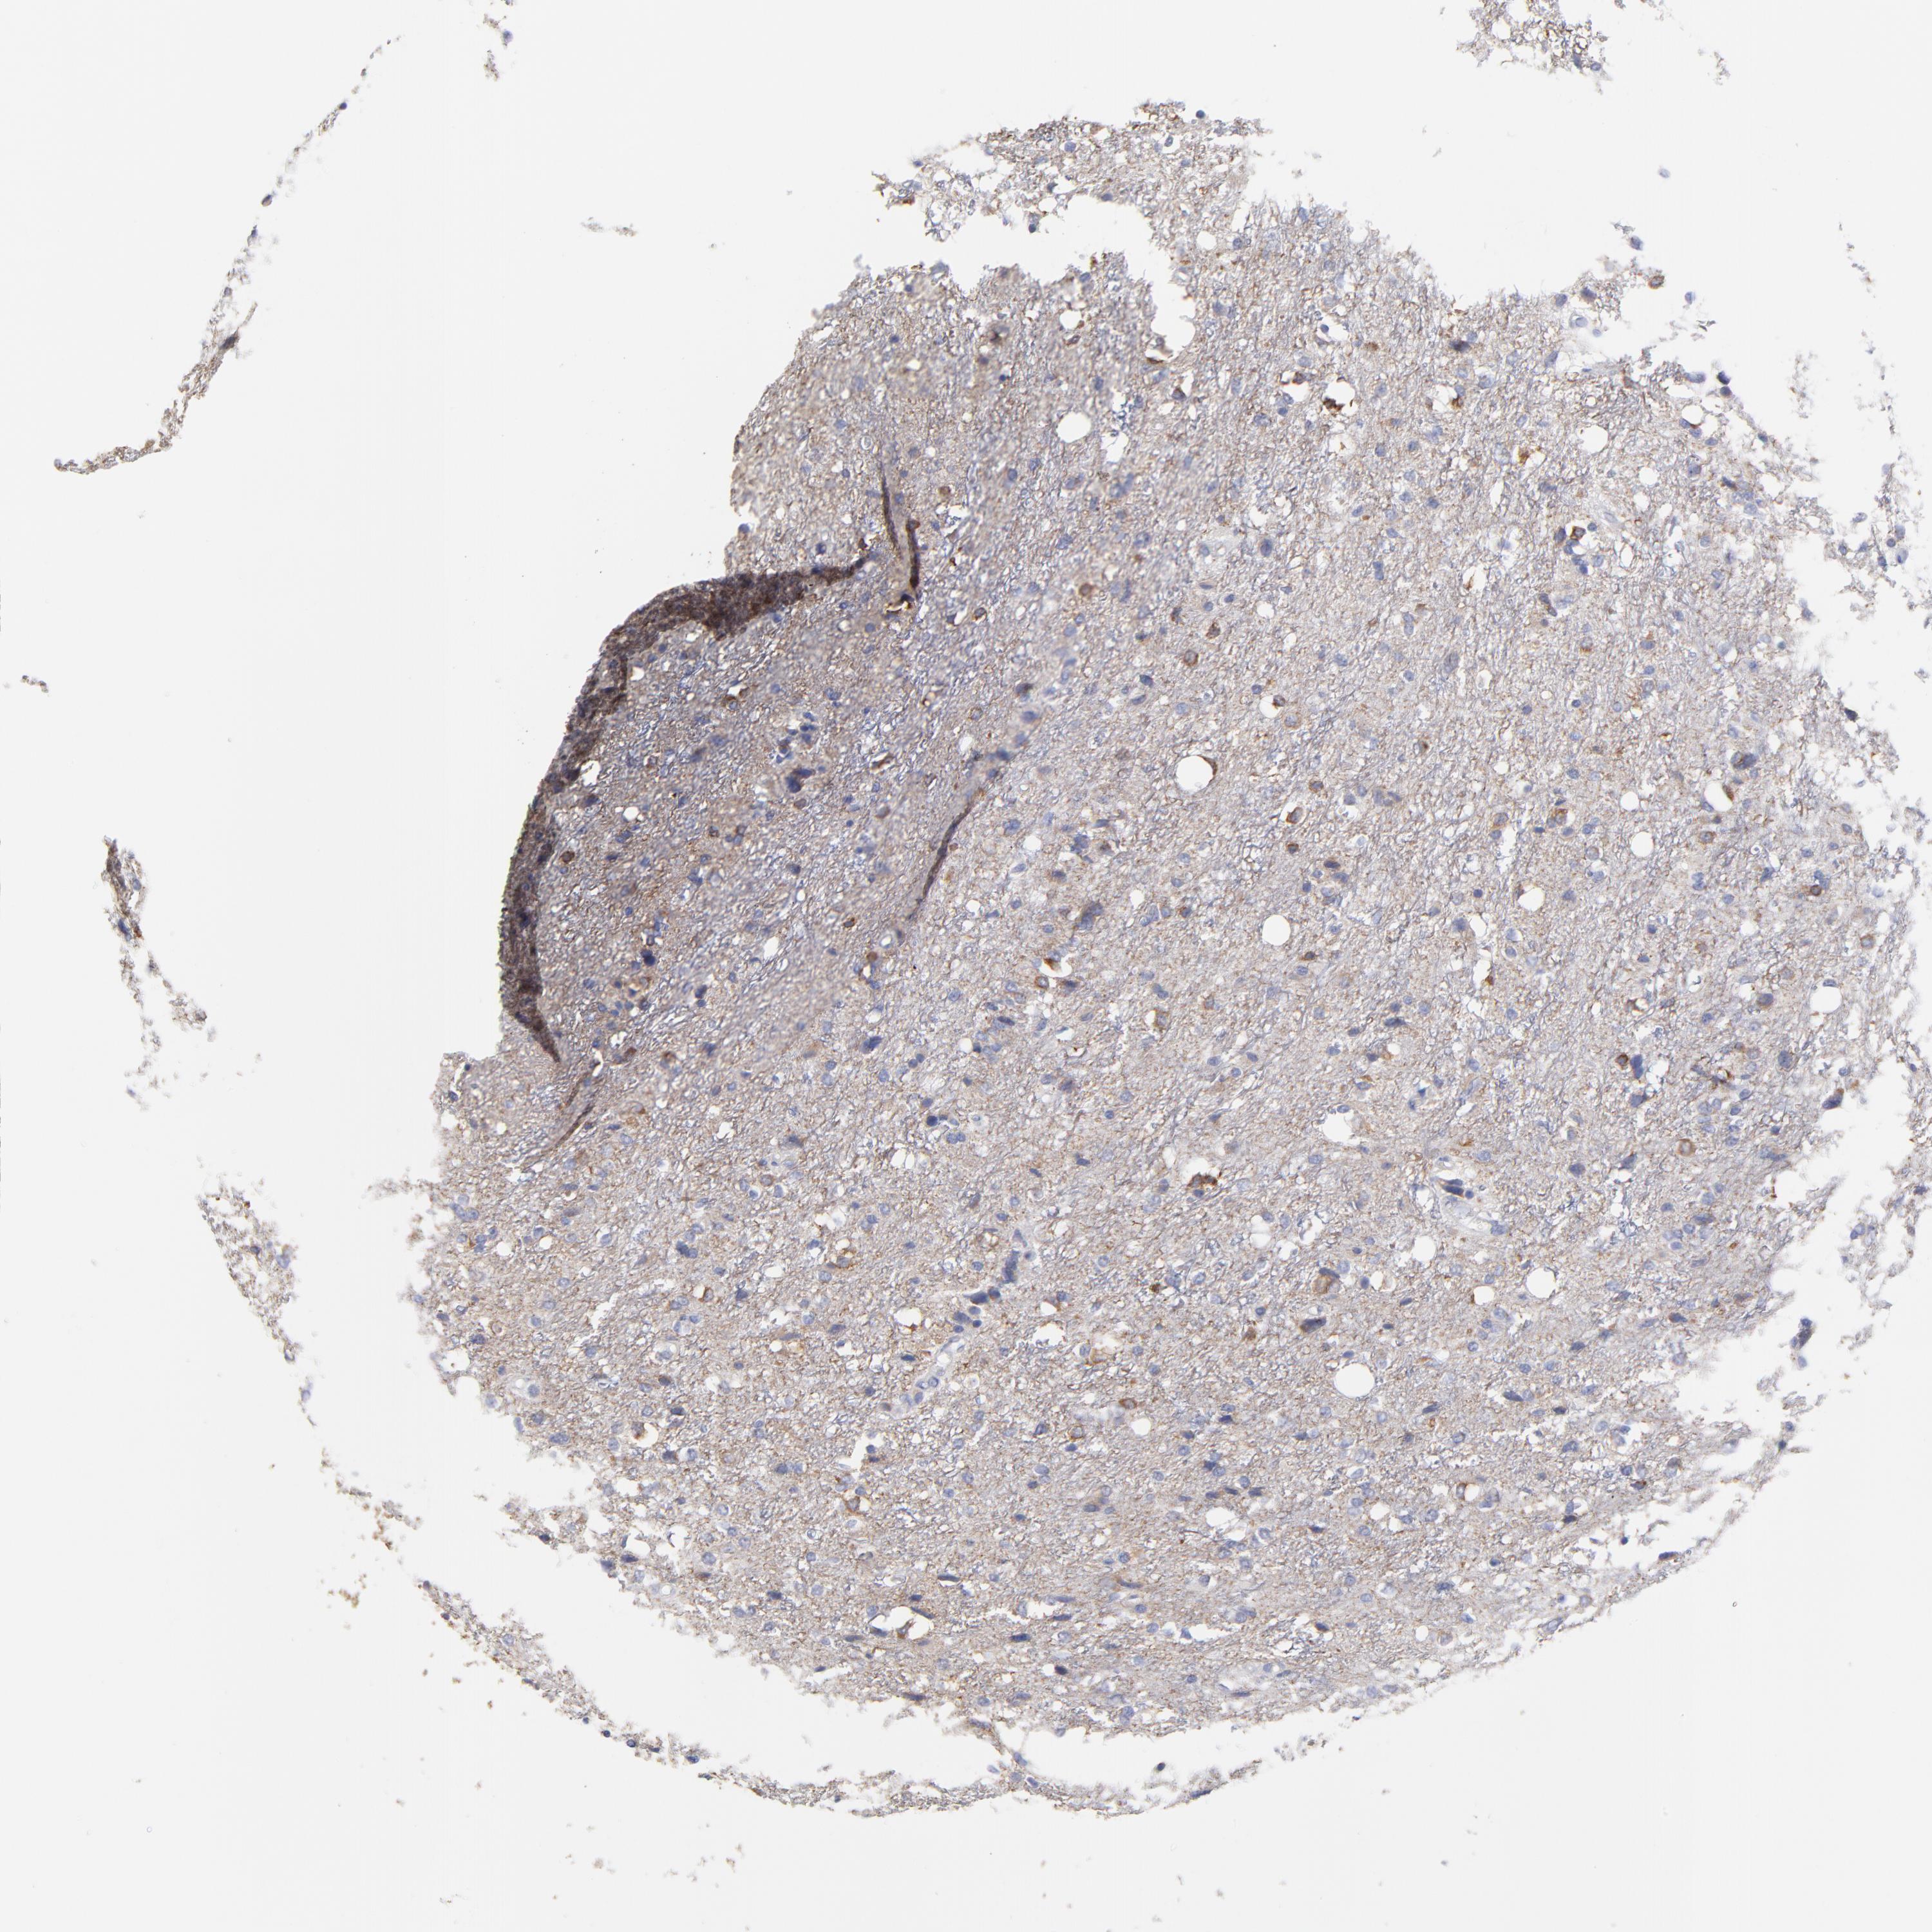

GLIOMA - Protein expressioni

A mouse-over function shows sample information and annotation data. Click on an image to view it in a full screen mode. Samples can be filtered based on level of antibody staining by selecting one or several of the following categories: high, medium, low and not detected. The assay and annotation is described here.

Note that samples used for immunohistochemistry by the Human Protein Atlas do not correspond to samples in the TCGA dataset.

Antibody stainingi

Antibody staining in the annotated cell types in the current human tissue is reported as not detected, low, medium, or high, based on conventional immunohistochemistry profiling in selected tissues. This score is based on the combination of the staining intensity and fraction of stained cells.

Each image is clickable and will lead to virtual microscopy that enables deeper exploration of all samples and also displays staining intensity scores, fraction scores and subcellular localization as well as patient and tissue information for each sample.

Antibody HPA003336

Staining

High

Medium

Low

Not detected

Intensity

Strong

Moderate

Weak

Negative

Quantity

>75%

75%-25%

<25%

None

Location

Nuclear

Cytoplasmic/membranous

Cytoplasmic/membranous,nuclear

Glioma, malignant, High grade

Glioma, malignant, NOS

Glioma, malignant, Low grade